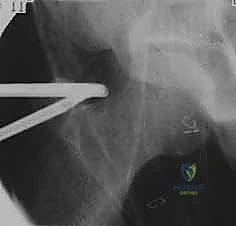

- الأشعة السينية (X-rays): لتقييم العظام، والتأكد من وجود نتوءات عظمية (FAI) أو علامات مبكرة لخشونة المفصل.

يتم غالباً استخدام التخدير العام أو النصفي. يوضع المريض على طاولة عمليات خاصة تُسمى (Traction Table). يتم سحب الساق برفق شديد لفتح مسافة صغيرة جداً في مفصل الورك (حوالي 1 سم) تسمح بإدخال الكاميرا والأدوات الجراحية بأمان دون إتلاف الغضروف.

2. إحداث الشقوق وإدخال الكاميرا

يتم عمل شقين أو ثلاثة شقوق صغيرة. يُضخ سائل معقم داخل المفصل لتوسيعه وغسل أي بقايا، ثم يتم إدخال كاميرا الألياف الضوئية (Arthroscopy) التي تنقل صورة مكبرة وعالية الدقة (4K) إلى شاشات العرض.